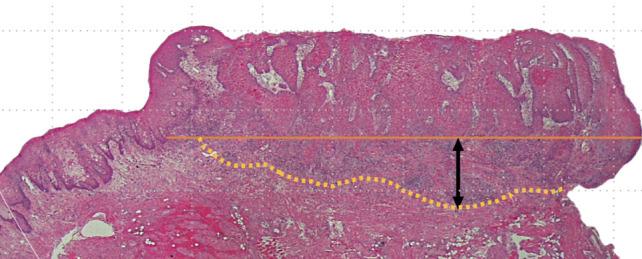

Multivariate analysis showed that the three parameters significantly correlated with CLM, and univariate analyses showed that budding score (BS) ≥ 5 and pathological depth of invasion (pDOI) ≥ 5 mm were independent risk factors for CLM. There were significant differences in the 5-year cumulative disease-specific survival between the BS < 5 and BS ≥ 5 groups, the pDOI < 5 mm and pDOI ≥ 5 mm groups, and the positive and negative budding and depth of invasion (BD) score groups.

In early-stage tongue and floor of the mouth cancers with maximum tumour diameter ≤ 20 mm, it may be necessary to treat occult CLM during initial surgery based on the following preoperative criteria: pDOI ≥ 5 mm or BS ≥ 5 in biopsy specimens and DOI ≥ 8 mm on imaging. The BD model exhibited the highest specificity and proved helpful for CLM prediction.

pDOI ≥ 5 mm and BS ≥ 5 were independent predictors of CLM and prognosis in early-stage tongue and floor of the mouth cancers with a maximum tumour diameter of 20 mm.